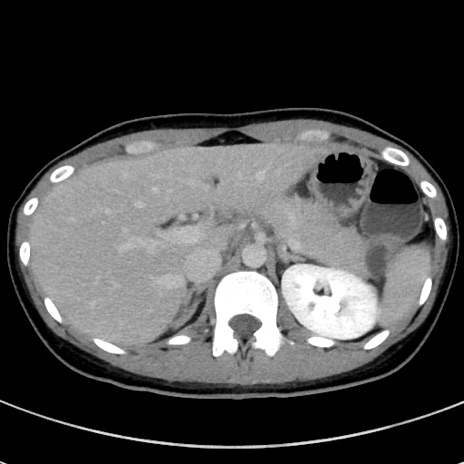

症例17(横断像)

【症例】20歳代女性

【主訴】嘔吐、下腹部痛

【現病歴】昨日夕食後に嘔吐し下腹部痛が出現。本日になっても嘔吐持続し改善しないため来院。

【身体所見】意識清明、BT 37.2℃、BP 108/67mmHg、腹部:平坦、やや硬、下腹部正中から右にかけて圧痛あり、反跳痛軽度あり、tapping pain(+)。

【データ】WBC 13600、CRP 14.94